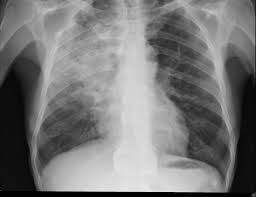

3. 흉부 X-레이: 흉부 X-레이 검사는 폐렴의 증거를 확인하기 위한 중요한 검사입니다. X-레이 영상에서 염증이나 독특한 패턴이 나타날 수 있으며, 이로써 폐렴 진단을 확인할 수 있습니다.